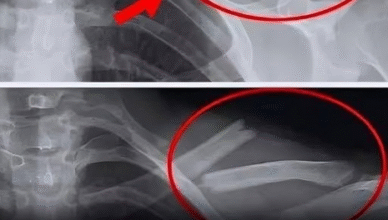

Новороздільська громада з глибоким сумом отримала звістку про непоправну втрату. Пішов із життя наш земляк, капітан медичної служби Олег Стефанович Костів. 30 вересня